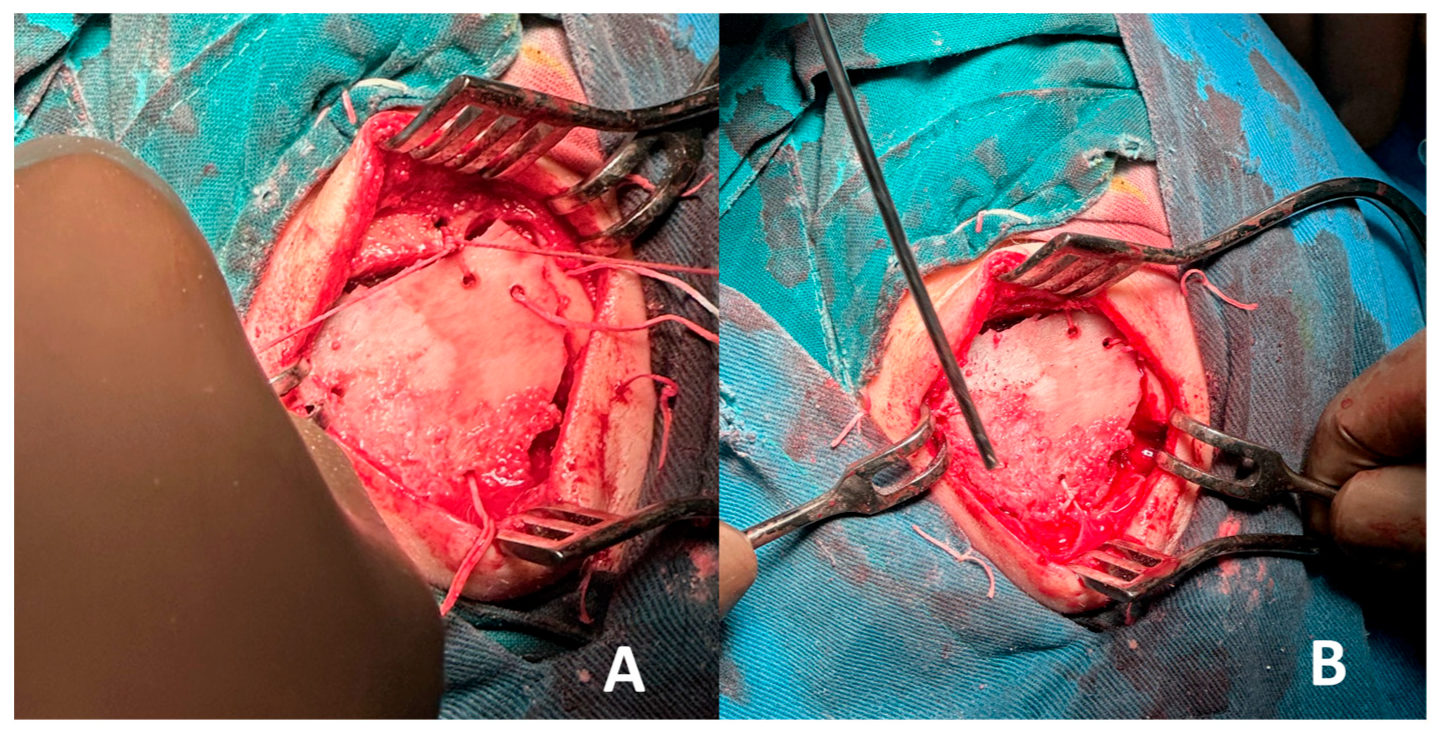

A local recurrence of the hemangioma was suspected, and the surgical treatment plan included complete excision of the lesion followed by reconstruction with autologous iliac crest bone. The patient had no history of chronic disease and was prepared for elective surgery. The patient was placed under general intubation anesthesia in the supine position on the operating table. Ultrasound was used for marking the tumor borders. A straight incision through the old surgical scar in the frontal region was performed. The tumor process was visualized, with significant protrusion, causing an aesthetic defect, as shown in Figure 3.

The frontal bone was exposed, and careful dissection of the overlying periosteum and surrounding soft tissues was performed to isolate the lesion. A craniotomy was then carried out by creating four burr holes strategically positioned around the lesion. These burr holes were subsequently connected using a bone saw to create a bone flap, allowing full access to the underlying lesion for en bloc excision. The technique ensured the preservation of adjacent structures and provided a controlled approach to remove the lesion with minimal trauma, as shown in Figure 4.

Figure 3. Vascular lesion, nearly 3 cm in diameter, affecting the diploe of the frontal bone: (A) central view; (B) side view.